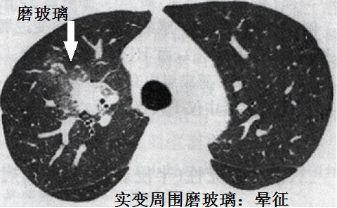

图7-8 胸部CT肺结核、军团菌、巨细胞病毒、肉芽肿、肺癌等有可能形成晕征,但是结合患者免疫力低下,对曲霉菌的特异性还是很高的。

免疫力低下,实变或者结节周围晕征,要高度怀疑血管侵袭性曲霉病。